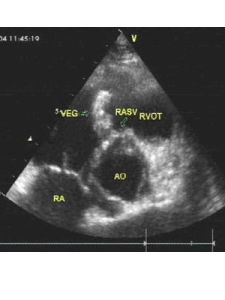

1.發病機制血流動力學改變造成的內皮損傷和菌血症的發生,是形成感染性心內膜炎最重要的機制,在正常情況下,如有少數病原體由口腔,鼻,咽部以及皮膚等部位進入血流後即被迅速消滅,當有器質性心血管病變時,病原體可在受損的心瓣膜,心內膜或血管內膜棲居,周圍有附著的血小板血栓及紅細胞和白細胞,並被纖維素所包裹而形成贅生物,形成心內膜炎症,心臟結構異常(如瓣膜狹窄或關閉不全,心內分流)引起的血流動力學改變是內皮損傷的基礎,機制為:高速噴射性血流衝擊內膜;瓣膜口狹窄形成壓力階差,大多數情況下內皮損傷發生在壓力階差的低壓側,菌血症的發生常由侵入性醫療操作引起,如牙周病手術後菌血症的發生率高達88%,內皮損傷後血小板與纖維蛋白聚集在損傷處,形成無菌性贅生物,如有菌血症發生,則形成感染性贅生物,贅生物一旦形成,在血流的持續衝擊下,將導致贅生物破碎和體內器官的栓塞。

(1)心臟及血管:本病的基本病理改變是心瓣膜,心內膜及大血管內膜表面附著疣狀感染性贅生物,活動期贅生物分3層:最裡層主要由血小板,纖維素,紅細胞,膠原纖維,壞死組織及細菌組成;中層由細菌組成;外層由纖維素與細菌組成,癒合期最外層被纖維素所覆蓋,中層及內層發生玻璃樣變與鈣化,心瓣膜的贅生物可造成瓣膜潰瘍及穿孔等,還可累及腱索及乳頭肌,使腱索縮短或斷裂,動脈瘤,巨大的贅生物可堵塞瓣膜口,導致急性循環障礙,贅生物受血流衝擊常有細微栓子脫落,由於栓子的大小及栓塞部位的不同,可發生不同的器官栓塞症狀並引起不同的後果,左心脫落的栓子引起腎,腦,脾,肢體和腸系膜動脈栓塞;右室的栓子引起肺栓塞,其中肺栓塞的發生率最高,微小栓子栓塞毛細血管產生皮膚瘀點,在小動脈引起內皮細胞增生及血管周圍炎症反應,形成皮膚的歐氏小結(Oslersnodes),感染性栓子栓塞後可發生以下變化: